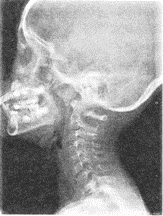

3.患者男性,5歲,反復嗆咳,張口呼吸,有鼾聲,鼻腔分泌物多。X線檢查如圖所見,最可能的診斷是

正確答案:D 解題思路:鼻咽腺樣體為位于鼻咽頂部的一團淋巴結(jié)組織,兒童期可呈生理性肥大,5歲左右最明顯,以后逐漸萎縮,至15歲左右達成人狀態(tài)。臨床上常見鼻塞、張口呼吸,入睡時有鼾聲。X線鼻咽側(cè)位片,見鼻咽頂后壁軟組織廣泛腫脹、增厚,表面柔軟光滑,鼻咽腔因腺樣體占位而狹小,局部骨質(zhì)無改變。